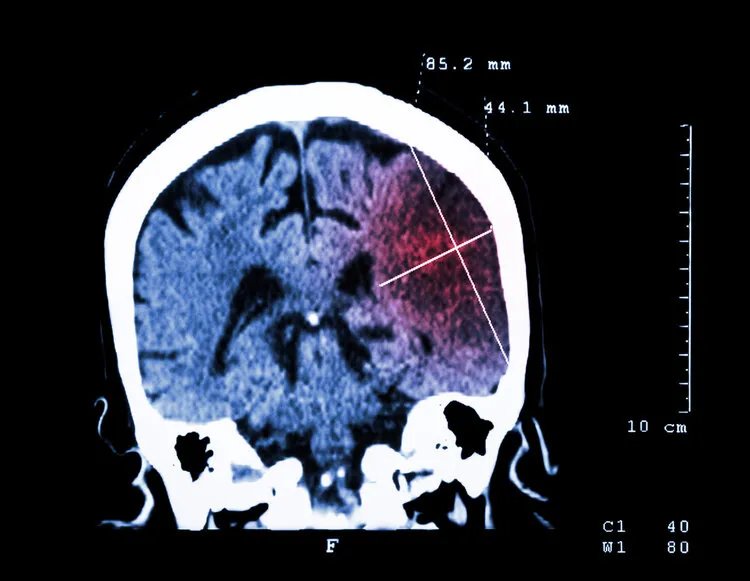

“识别出中风之后,家属不要瞎折腾,应该马上拨打120。”彭忠兴指出,中风分为脑出血和脑梗塞两种,如果不做CT等检查,无法准确判断。自行给病人吃安宫牛黄丸、喂参汤、含参片、喂糖水、按摩摇晃等做法都是错误的。